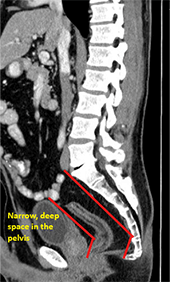

Image of a scan.

An advantage of the robotic surgical system is that it gives surgeons better access to operate minimally invasively in the pelvis.

“It's like operating inside of a glass – reaching down a closed, rigid cylinder-type space,” describes Dr. Whelan. “If laparoscopy doesn't work and you must convert to an open procedure, that extends recovery time and increases pain and future adhesions. If you can use the robot to rescue that minimally invasive approach and keep it that way, I think that's really where it shines.”